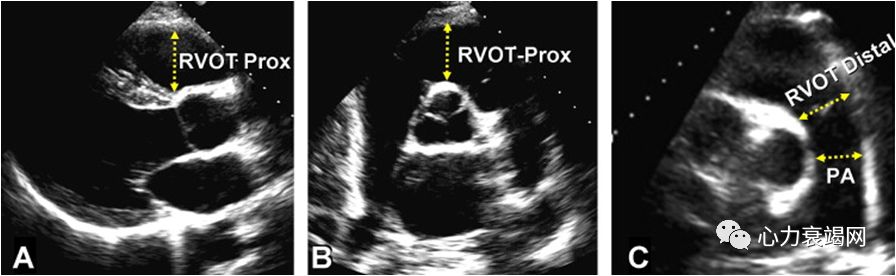

RVOT Prox 内径 > 33 mm, RVOT Distal 内径 > 27 mm。